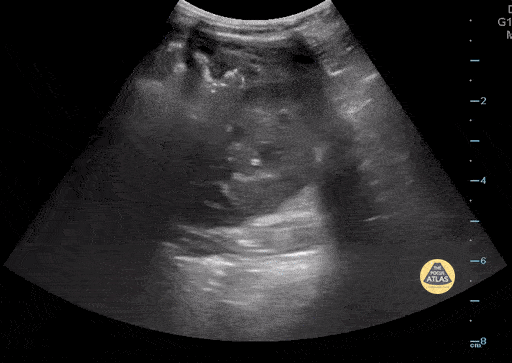

18 mo F sent from PMD for mass in the RUQ. POCUS shows extra renal mass consistent with neuroblastoma that was later confirmed by pathology. Contributor: Paul Khalil, MD Nicklaus Children's Hospital